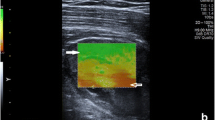

Two experienced readers (blinded to each other) independently scanned a single lesion per patient. Reader 1 (R1) was a board-qualified radiologist (author 4) with >18 years experience (>3 years with SWE). Reader 2 (R2) was a board-qualified sonographer (author 2) with 5 years experience (>2 years with SWE). Patients were placed in relaxed positions depending on the location of the lesion. Positions were adjusted to ensure no active (contraction) or passive (stretching) effects directly influenced the elasticity results. R1 marked the skin surface to determine transducer location and this was also used to place the probe by R2. Each reader made five measurements of shear wave velocity (m/s) and stiffness (kPa) in the transverse and craniocaudal (CC) planes from the most homogenously solid and vascularised region. The same region of the lesion was sampled each time. The probe was lightly replaced between each measurement using minimal probe pressure on the skin surface. Each reader defined the region of interest using a modifiable square box located in the most superficial aspect of the lesion that appeared solid (Fig. 1). Depth of measurement (cm) was recorded for each lesion and for each reader. Lesion volume (cm3) was also recorded for each lesion.